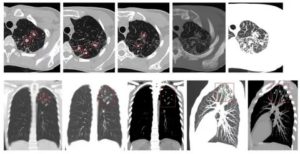

В числе наиболее эффективных способов определения туберкулезного заболевания на ранних стадиях его развития является компьютерная томография. Первичный туберкулез на КТ легких отображается в виде разрастаний на корнях органов дыхания. Еще врач может заметить следы патологических изменений тканей.

При выполнении тестов делают снимки с разных ракурсов и проекций. Потом специалист изучает результаты и составляет подробное описание.